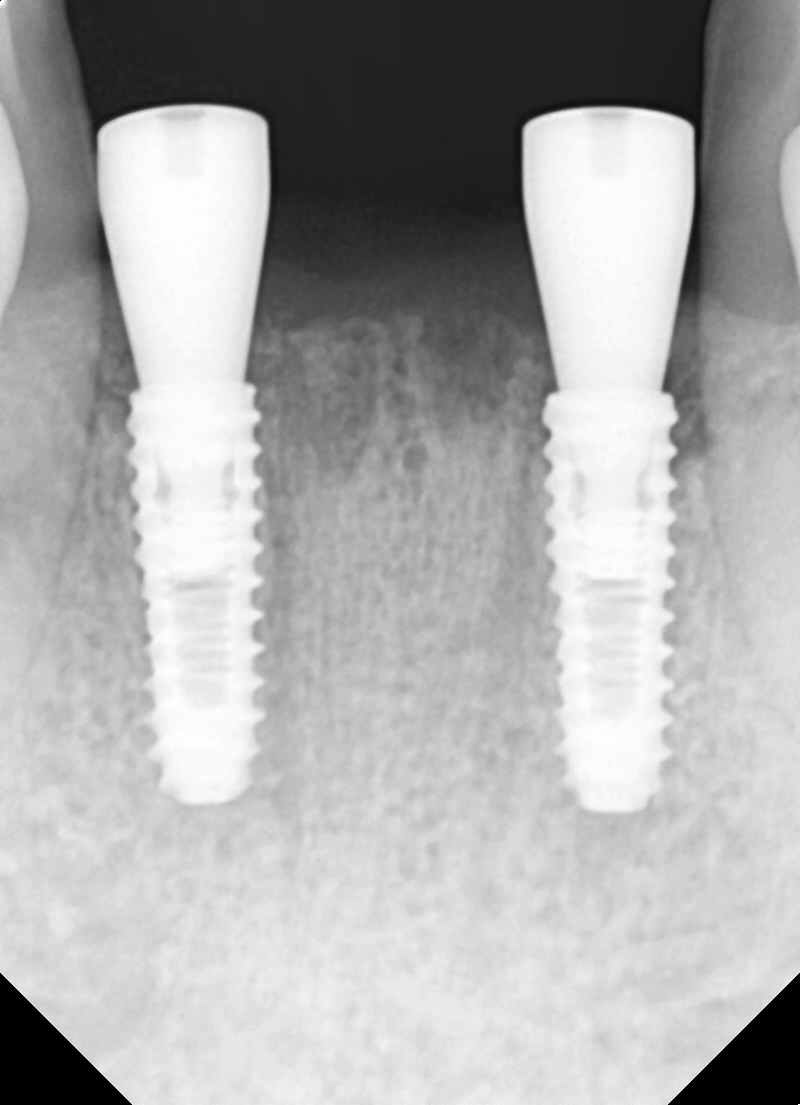

어쩔수 없이 4개의 아래 앞니를 발치 한 후 당일 2개의 임플란트를 식립했습니다.

3개월 정도 지난 후 최종 보철물을 완료해드렸습니다.